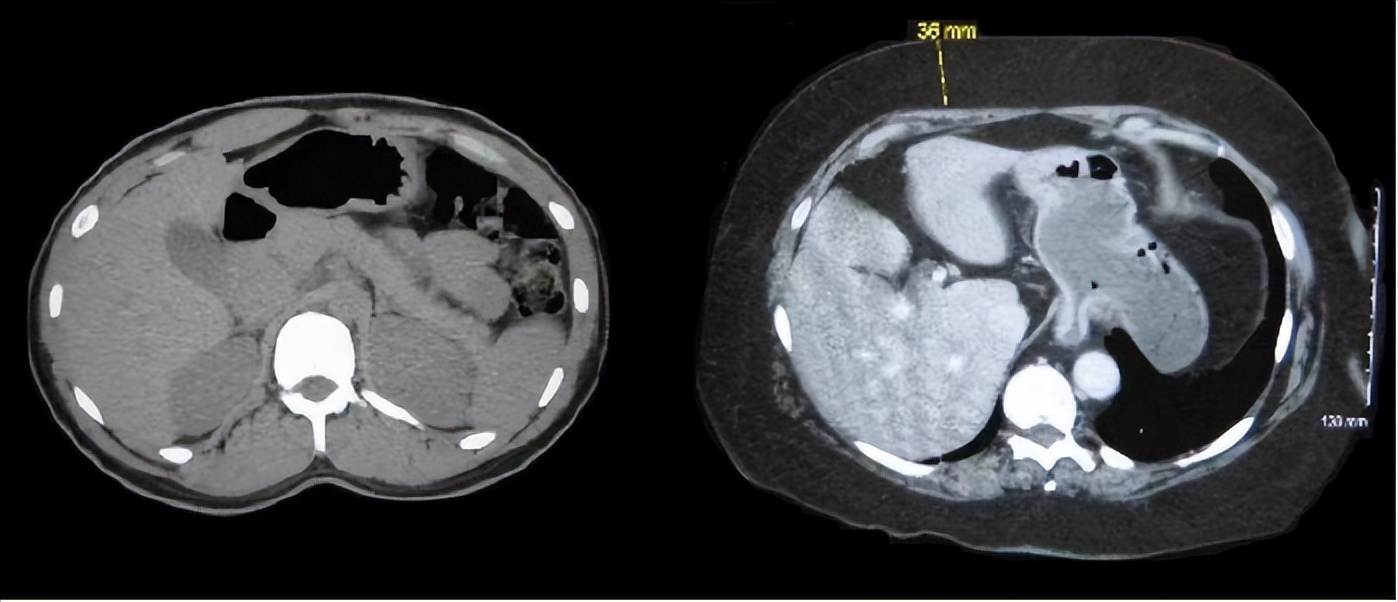

左边是体重正常人的腹部CT,右边是肥胖症患者的腹部CT,其皮下脂肪厚度足有3.6cm。 图源 | 维基百科